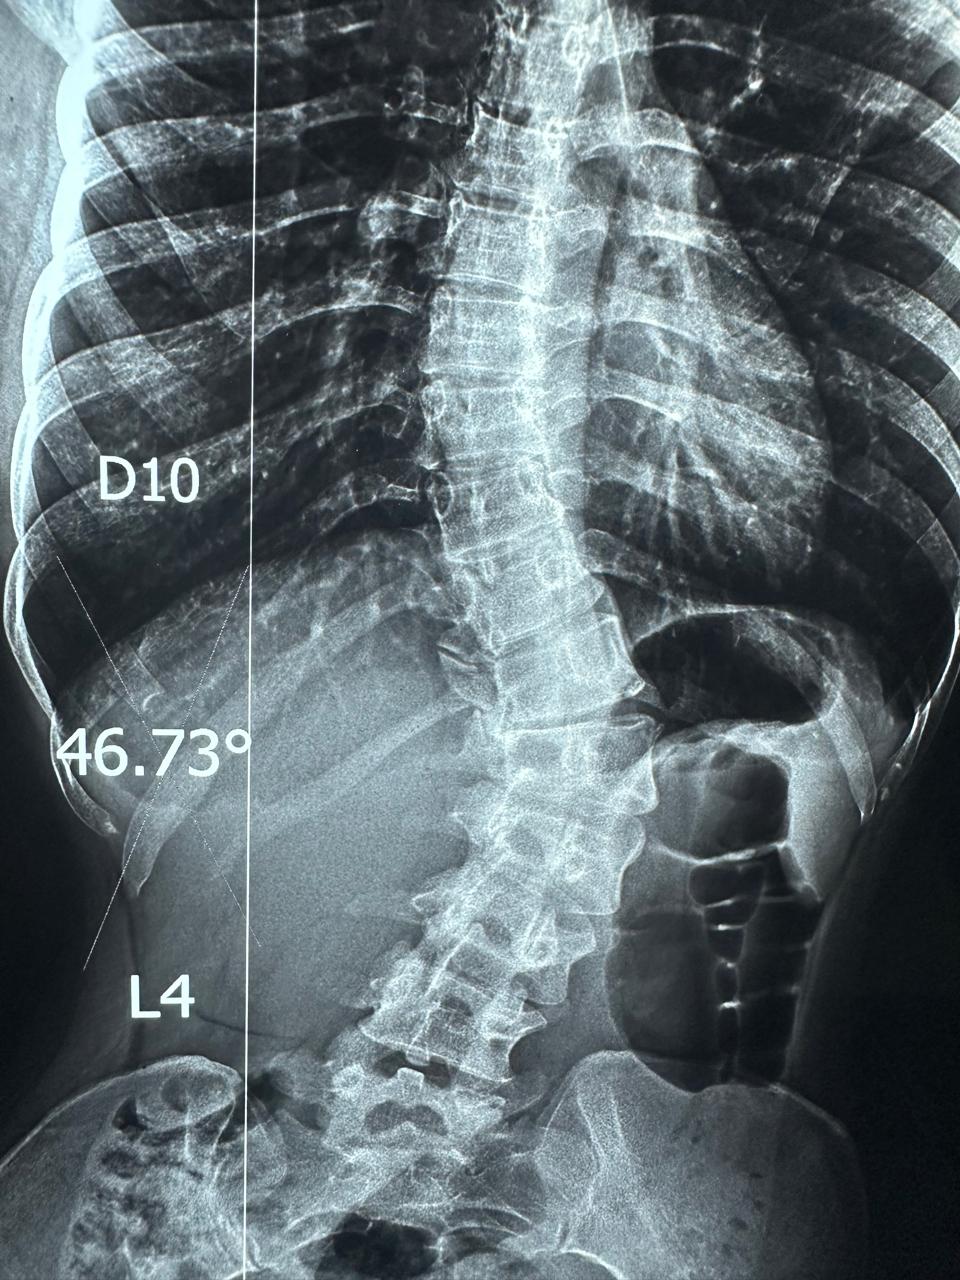

نجح الفريق الطبي بمستشفى قليوب التخصصي في تحقيق إنجاز طبي جديد، وذلك بعد تمكّنه من إجراء عملية دقيقة لمريضة كانت تعاني من اعوجاج شديد بالعمود الفقري، حيث تم إصلاح وتشريح الاعوجاج وتثبيت الفقرات باستخدام 20 مسمارًا معدنيًا لضمان ثبات واستقامة العمود الفقري.